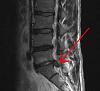

Deciding whether to have an MRI scan or an X-ray can be a difficult decision. Many of us will want to make sure that there is nothing serious the matter and doctors may feel the same. The problem with MRI scans is that they cost more to perform and may well end up highlighting normal changes. This can increase worry and may lead to unnecessary surgery..

This page talks in a bit more detail about the differences between the two types of investigation.

This website has a nice article looking to see if having an MRI scan meant better outcomes for a group of patients with back pain. Surprisingly, there was no difference.

Once you have the diagnosis finding the exact tissue that is the source of your pain is much harder. X-rays and MRI scans only tell half the story and you may find that a very precise diagnosis is not possible. Find out more about how you diagnose simple back pain here.